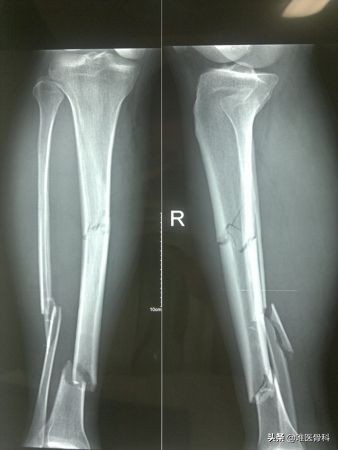

1.X线检查

凡疑为骨折者应常规进行X线拍片检查,可显示临床上难以发现的不完全性骨折、深部骨折、关节内骨折和小的撕脱性骨折等,即使临床上已表现为明显骨折者,X线拍片检查也是必需的,可以了解骨折的类型和具体情况,对治疗具有指导意义。

X线摄片应包括正、侧位片,必须包括邻近关节,有时需加摄斜位、切线位,行健侧相应部位的X线片可做对比。